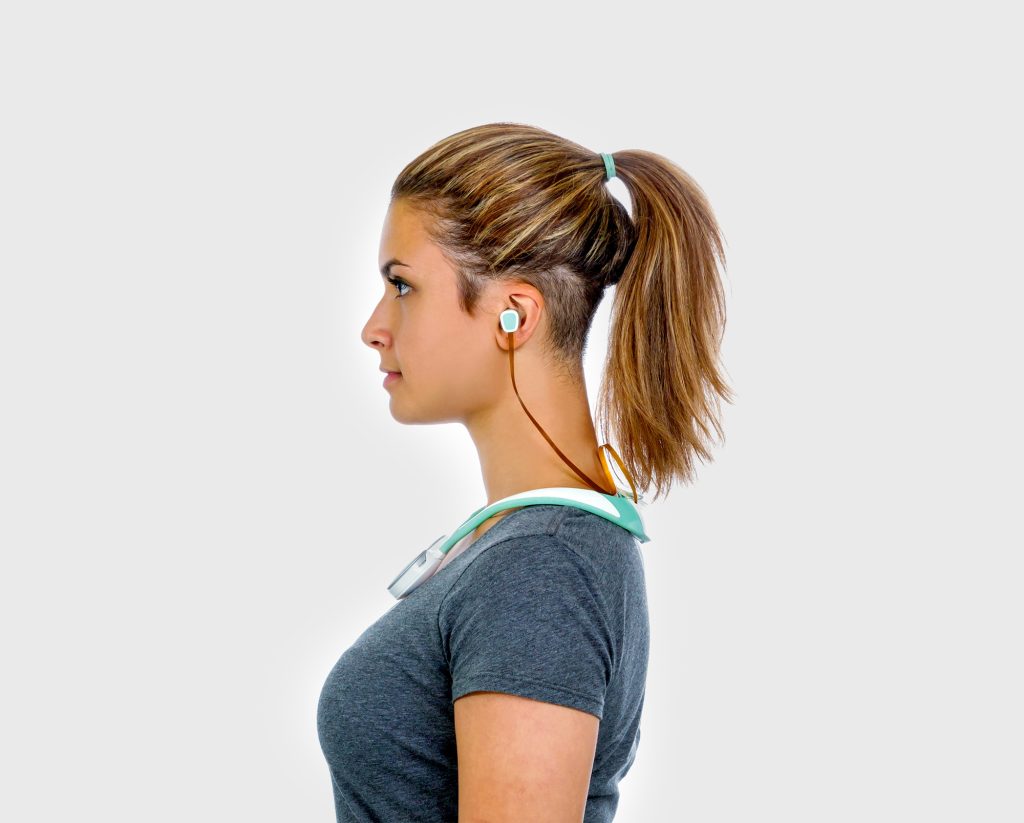

VITALITI is a “doctor in a box” – a wearable medical device paired with a diagnostic basestation that can diagnose 19 chronic medical conditions, monitor all 5 human vital signs, and stream that data to a cloud server – all without a clinician. And it had to weigh less than 5 lbs too. It is poised to disrupt overstressed healthcare systems and super-empower users by assessing physical wellness outside of clinical settings.

- How to bridge several data collection points on a patient’s collarbone and ear in a single wearable.

- The wearable had to collect all five human vital signs continuously for three days. We realized our wearable had to be easy to charge without the user having to take it off.